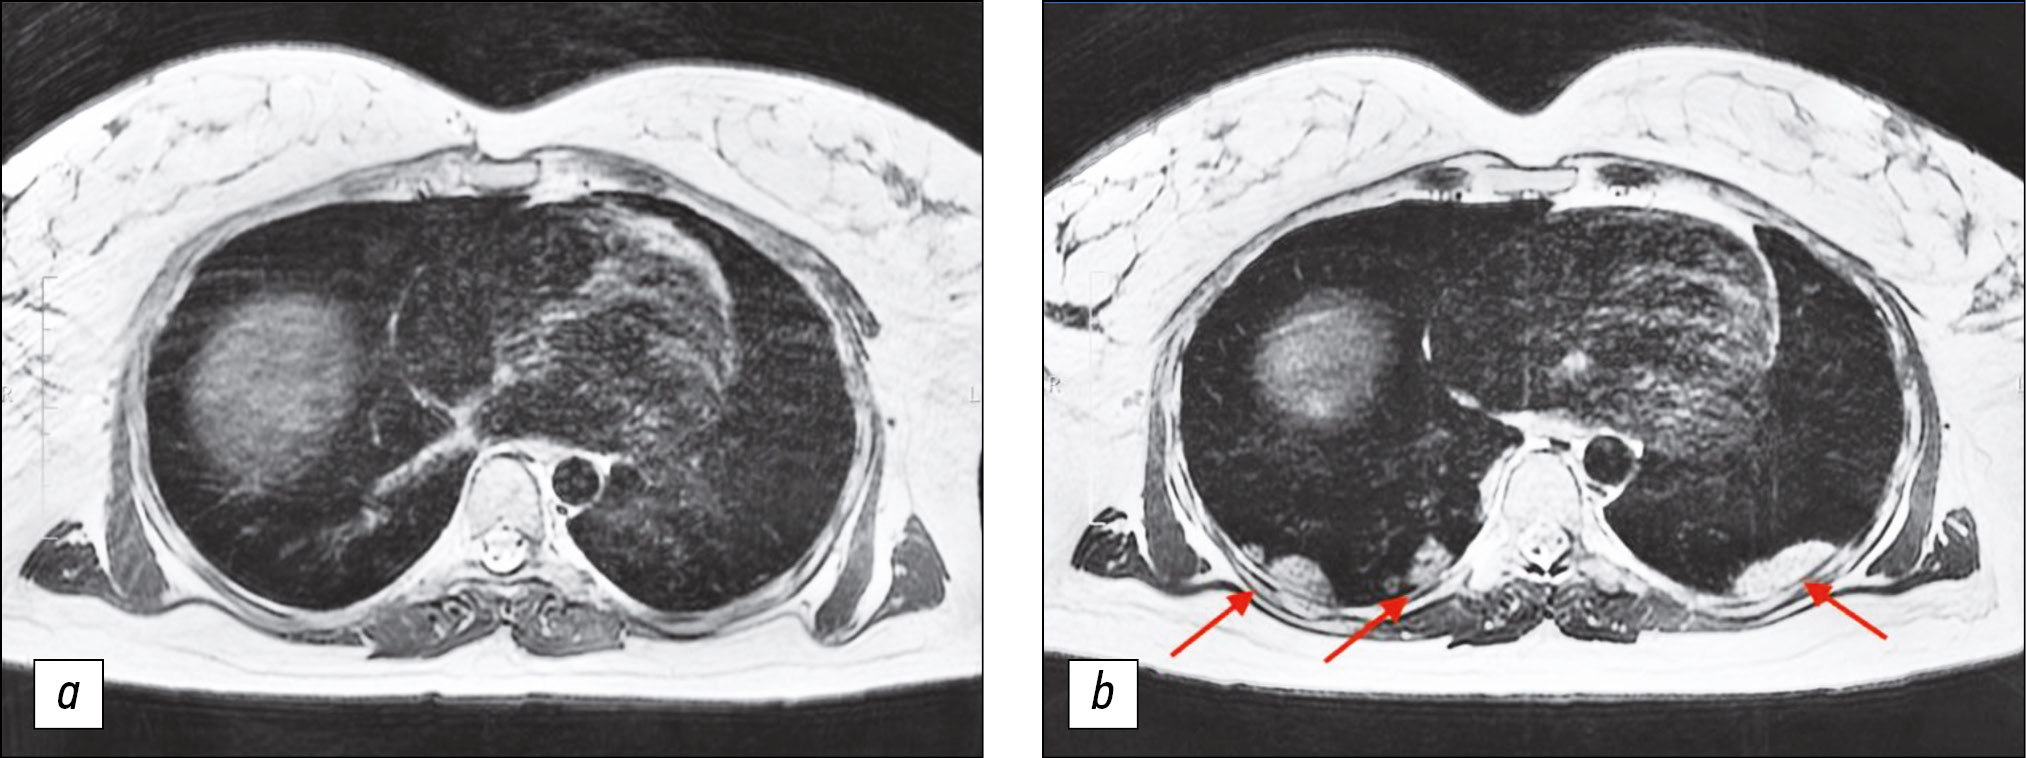

Lung MRI was performed 7 days later, because the condition did not improve during treatment, and dry, ineffective cough worsened. MRI performed that time revealed zones of infiltration (Figs. 1, 2) in the lower lobes of the lungs.

Figure 1. Chest magnetic resonance imaging, T2-weighted imaging single-shot fast spin echo: a) Primary examination, b) magnetic resonance imaging 7 days later. In Fig. 1b, consolidation zones in lower lungs appeared as areas of hyperintense and isointense signals.